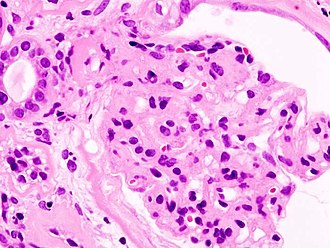

Nodular glomerulosclerosis in diabetes, a common cause of chronic renal failure. H&E stain. (WC/KGH)